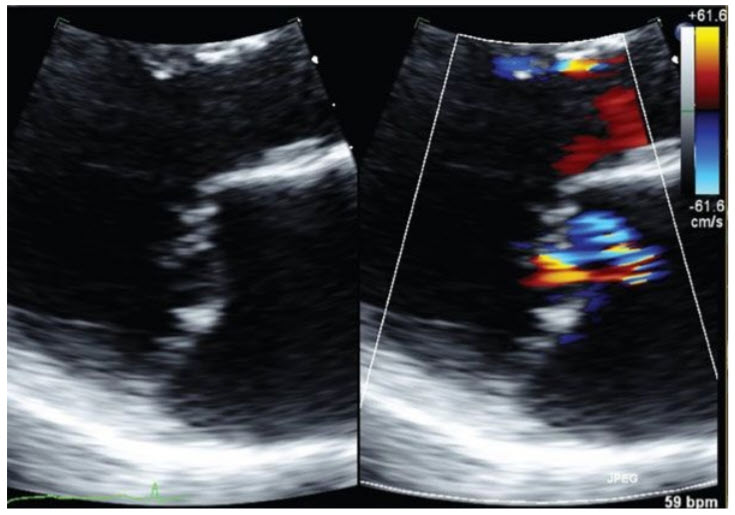

An echocardiogram is performed on this patient (Fig. below).

Left ventricular (LV) systolic dimension is 4.7 cm. Ejection fraction is 45%. There is posterior leaflet prolapse. There is a very eccentric jet of MR, which is read out as 2+.

Which of the following is most likely?

She likely has more severe MR than is evident on the echocardiogram. Her examination is suggestive of severe MR. The echo confirms LV dilation and mitral leaflet pathology, which could be consistent. The eccentric nature of the jet suggests that it may have been underestimated by transthoracic imaging. A more definitive imaging procedure such as TEE will be helpful here.